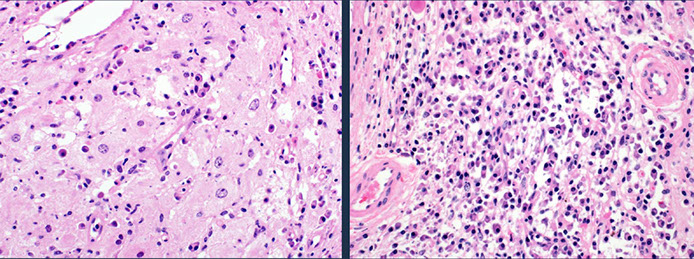

Reactive Paracortical Hyperplasia

Expansion of paracortex from T-cells proliferation, which can be due to drugs, viruses and vaccines

- architecture is preserved

- Immunoblasts in a sea of small T cells and histiocytes (immunoblasts can be CD30+, but this is not Hodgkins!!)

- assoc c viral infx, post-vaccine lymphadenitis, Infectious mononucleosis (EBV), drug-induced hypersensitivity, dermatopathic lymphadenitis, histiocytic necrotizing lymphadenitis, SLE

Micro: T-cells appear monomorphous, small and mature appearing

- have almost evenly-spaced scattered interdigitating dendritic cells sprinkled throughout that gives it a mottled-effect

Reactive paracortical hyperplasia [3]. Hyperplasia of the paracortex outside of follicles. Can have vaguely nodular areas of enlargement of the paracortex. The T-cells appear monomorphous, small and mature appearing. Have almost evenly-spaced scattered interdigitating dendritic cells sprinkled throughout that gives it a mottled-effect